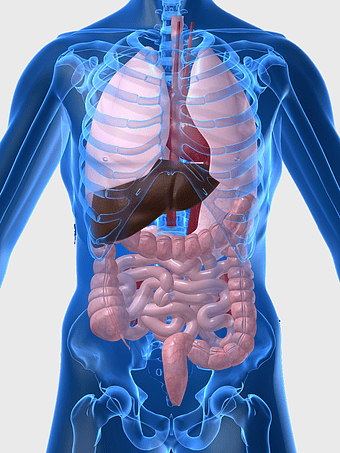

human digestive system, gastrointestinal tract anatomy, liver function, stomach and intestines, digestive health, internal organs diagram, human body systems -

human gastrointestinal tract anatomy, human digestive system illustration, gastrointestinal disease symptoms, human body organ diagram, internal organ visualization, medical anatomy study, digestive health awareness -

human internal organs chart, gastroenterology anatomy diagram, electric blue human anatomy, liver and stomach illustration, digestive system visualization, medical organ study, human body internal structure -

human anatomy diagram, digestive system illustration, human internal organs, Homo sapiens muscular system, anatomical art for education, systemic physiology chart, medical biology graphics -

human digestive system illustration, gastrointestinal tract diagram, human body organ system, labeled digestive system, digestive anatomy chart, human internal organs, alimentary canal visualization -

digestive system diagram, gastrointestinal tract chart, human anatomy illustration, small intestine function, digestive process visualization, internal organ layout, metabolic system overview -

human digestive system anatomy, gastrointestinal tract illustration, stomach muscular layer, abdominal organ diagram, digestive health education, medical biology study, internal human body structures -

Large intestine anatomy, gastrointestinal tract illustration, small intestine diagram, human digestive system structure, colon health, digestive organs, internal anatomy chart -